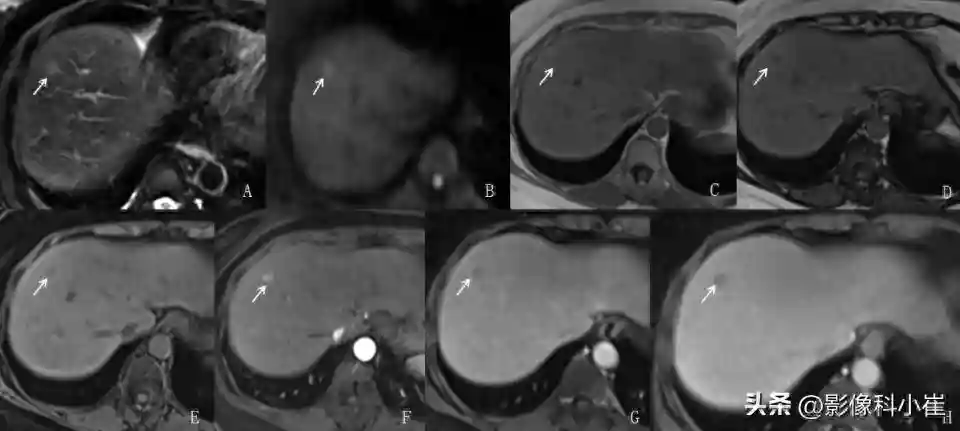

图AT2WI-FS图BDWI图CT1WI图D反相位

图ET1WI-FS图F动脉期图G静脉期图H平衡期

MRI上HCC分型与病理分型相同,病灶T1WI为略低或等信号,瘤内脂肪变性、出血、坏死囊变时信号不均,脂肪变性是HCC的特征之一,可利用同反相位显示该特点;T2WI呈略高信号,T2WI-FS显示更清晰;边界清晰或不清,DWI及ADC示弥散受限。增强扫描动脉期明显强化呈相对高信号,静脉期强化程度迅速下降,呈略低信号,平衡期强化程度继续下降呈低信号,总体呈“快进快出”强化方式。肝胆特异期呈低信号。

假包膜是HCC另一特征,包膜为肿瘤膨胀生长时周围肝实质受压所致,T1WI较敏感,表现为周围周围低信号环,增强扫描门脉期及延迟期包膜强化较清晰。